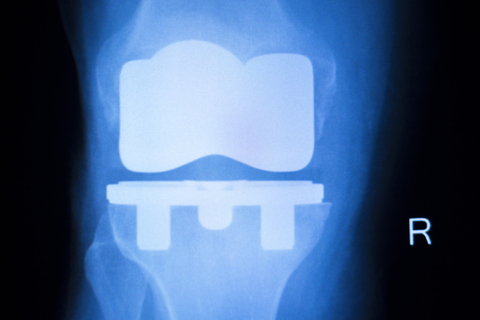

Knee Problems, Faulty Implants and Patient Safety: What You Should Know

Knee replacement surgery has transformed the lives of thousands of people across the UK, with most patients experiencing excellent long-term results and implants typically lasting 15–20 years or more. Research indicates that approximately 5% of total knee replacements (TKA) may necessitate revision surgery within 10 years. The most common reasons include aseptic loosening (29.8%), infection (14.8%), and ongoing pain (9.5%). While these risks remain relatively low, they can have a significant impact on the individuals affected.

Each year, the NHS carries out a large number of knee replacements, and the majority of implants are both safe and effective. However, data from the National Joint Registry has occasionally highlighted certain implant models with higher-than-expected revision rates, such as the NexGen knee implant, which was withdrawn in 2022. This underscores the wrongful selection of the implant and establishes  the importance of continual monitoring and patient safety in joint replacement care.